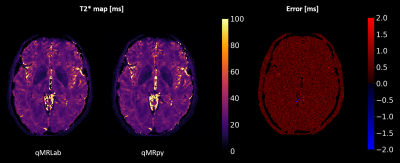

Validation and benchmark: To validate our software, we computed T2* maps from multi-echo Gradient Echo data (whole brain coverage, 200x200x200 matrix size for a 1 mm isotropic resolution, 9 echoes, TEmin = 3.3ms, echo spacing = 3.6ms) of an healthy volunteer, acquired on a GE Healthcare Signa 7T scanner using a 2-channels Tx / 32-channels Rx head coil. As a reference, we computed T2* maps using qMRLab, a flexible and well-established toolbox for qMRI mapping written in MATLAB/Octave. Fitting was restricted to the voxels with a magnitude higher than 5% of the maximum, and the same mask was used both for qMRpy and qMRLab fittings. Quantification accuracy of qMRpy was measured assuming the result of qMRLab as the ground truth, and the two softwares were compared in terms of execution time on a Linux workstation equipped with a 24 cores CPU (with 2 threads per core) and 128 GB of RAM.

Figure 4 shows the comparison between qMRpy and qMRLab derived T2* maps. The two implementations provide the same result, as the voxel wise difference remains below 2ms except for some voxels belonging to CSF where the fit is not well-conditioned. In terms of execution times, qMRpy outperforms qMRLab, reaching an order of magnitude of speed-up thanks to the parallelization enabled by Numba. As the codebase is based on pure Python, without low-level language extensions, the package is easy to customize and to distribute to different platforms, and does not require the purchase of expensive licenses. Thanks to its Command Line Interface, qMRpy-based routines can be easily integrated in automated (e.g., bash-based) pipelines, and its flexible I/O module allows for examination of the reconstructed maps on both vendor-provided and third-party image viewers.

Figure 4. Validation of qMRpy T2* mapping, compared to qMRLab (assumed as ground truth). It can be seen that qMRpy provides correct quantification, the error being less than 2ms in the whole brain mask except for some voxels belonging to CSF where fit is not well conditioned.